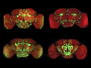

Male infertility contributes to around half of infertility cases. There are many reasons why men can be infertile, including the production of low-quality sperm, low sperm count or low levels of testosterone. Polycomb Repressive Complex 1 (PRC1) is a protein complex known to be involved, as its name suggests, in silencing the production of certain proteins from their gene. However, in a mouse model, PRC1 was found to change once males reached reproductive age and activate certain genes responsible for triggering fertile sperm. The change in PRC1 involved the addition of another protein called Sall4 (pictured in green in a testicular section) to initiate the timely production of fertile sperm. When PRC1 is disrupted in mice, they’re unable to produce healthy sperm nor, therefore, reproduce. This finding will help researchers to dig deeper into genetic factors affecting infertility.